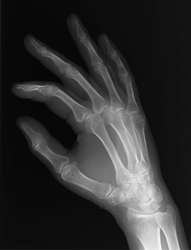

Die Regeneration von Knochengewebe wird derzeit aktiv erforscht und kann den weltweit fast 75 Millionen Menschen, die an Erkrankungen der Muskeln und des Bewegungsapparates leiden, neue Chancen bieten. Eine EU-finanzierte Initiative führt zur Entwicklung neuer Biowerkstoffe, die eine verbesserte Knochenbildung sowie eine bessere Versorgung des neuen Gewebes mit Sauerstoff und Blut für eine dauerhafte Funktion versprechen.

Der Aufbau neuer bzw. die Heilung verletzter Knochen ist mit dem Bau eines Haus vergleichbar. Dabei wird jeweils geeignetes Werkzeug für die Herstellung von Ziegeln und Mörtel, die Installationsarbeiten und die Belüftung benötigt. Zur Regeneration von Knochengewebe muss daher zunächst eine Art dreidimensionales, poröses Biogerüst aufgebaut werden, um das Anwachsen neuer Zellen zu verbessern und eine ausreichende Versorgung der Kapillargefäße mit Sauerstoff und Blut zur Nährstoffversorgung und zum Abtransport von Abfallstoffen. Das Projekt "Intelligent and reinforced tissue scaffolds for regenerative biomedicine" (Biosca) trug zur Entwicklung einer neuen Generation biokompatibler Werkstoffe bei. Diese wiesen sowohl die erforderliche Reaktivität zur Unterstützung des Zellwachstums als auch genügende Porosität für eine 3D-Kolonisation der tiefen Bereiche des Gerüsts auf. Zunächst entwickelten die Wissenschaftler neue Bioverbundwerkstoffe auf Basis von Kohlenstoffnanoröhren und mesoporöser Kieselerde. Dadurch wurde die Leitfähigkeit verachtfacht (um den Faktor 100 Millionen vervielfacht). Dies führte zur elektrischen Stimulation und Aktivierung von knochenbildenden Zellen (osteoblastenähnlichen) Zellen durch viel geringere Ströme. Darüber hinaus bildete die Erforschung von Hydroxylapatit (HA)-Systemen für die Knochenregeneration und Knochenimplantatintegration einen Schwerpunkt des Projekts. HA ist ein in der Natur vorkommendes kalziumhaltiges Mineral und einer der Bestandteile der Knochenmatrix. Es wurden neue HA-Beschichtungen entwickelt, deren Oberfläche durch Poren vergrößert wurden (so wie ein Glasträger mit zahlreichen kleinen Hohlräumen mehr Wasser fasst als einer ohne Hohlräume). So wurde also nicht nur die Kontaktoberfläche für das neue Knochengewebe vergrößert, sondern es konnten auch biologisch aktive Moleküle wie Wachstumsfaktoren aufgebracht werden, die das Anwachsen und das Wachstum der Zellen weiter verbessern könnten. Durch die Porosität werden die Sauerstoffzufuhr des Gewebes und die Versorgung durch Kapillargefäße verbessert. Diese sind für die Gesunderhaltung des Gewebes wesentlich. In-vivo-Experimente mit neuen HA-3D-Schäumen wiesen zusätzlich zu ihren biochemischen Eigenschaften verbesserte mechanische Eigenschaften auf. Insgesamt erzielte das Biosca-Projekt bedeutende Fortschritte auf dem Gebiet der Knochenregeneration mit zusätzlichen Einsatzgebieten von der Schwermetallausleitung bis zur Tumortherapie. Weitere Erforschung und Vermarktung dieser Innovationen könnte die Lebensqualität von Millionen Menschen, die an Erkrankungen des Bewegungsapparates leiden, steigern und europäischen Unternehmen im Bereich der Biowissenschaften einen Wettbewerbsvorteil verschaffen.